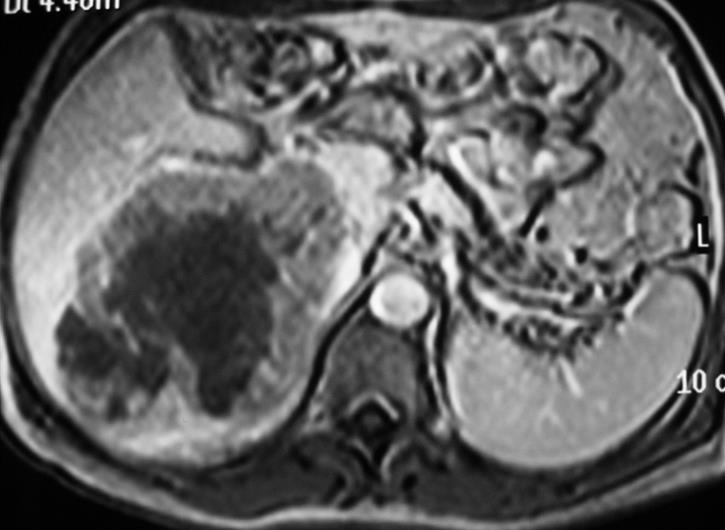

男,49,巨大肝癌,DEB-TACE

MRI 显示完全坏死,29个月没有复发。